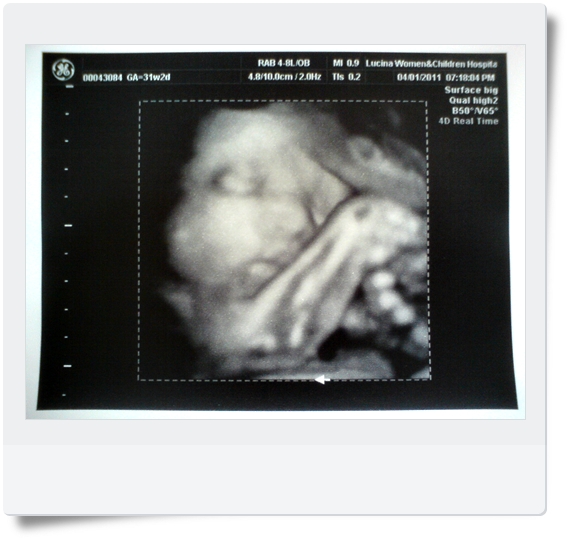

上回是第30周產檢時有拍,不過小麵將不太合作,拍起來挺像外星人的

這周看起來稍有人樣,所以選擇漂亮的給大家看看 :)

第32周,小麵將目前1545g,據上次產檢(第30周)時增加了250g左右 ^^

(剛去查了一下,比姐姐還瘦小耶~"~ 小石頭第31周是1632g啊~~~)

對了,下圖是小石頭第29周時拍的4D超音波

媽咪的感想:在肚子裡的BABY好像都長得差不多................哈哈哈哈~~~~~~~~